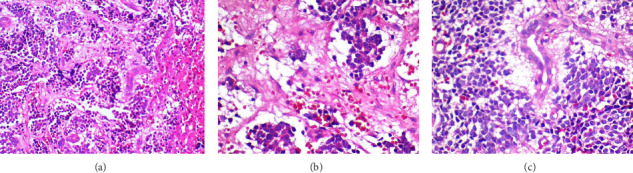

Infantile hepatic hemangioma (IHH) is rare, but the most common benign hepatic tumor in the first year of life. It has a characteristic course with perinatal presentation, increasing growth during the first year of life, and subsequent shrinkage of the vascular lesions. The authors report a 12-month-old male infant who presented with severe abdominal distension and respiratory distress while under workup for diffuse IHH since 2 months of age. In addition, the child's situation was complicated by two uncommon occurrences: bilateral chylothorax and the presence of neuroblasts and rosette cells in the pleural fluid. The detection of such cells in pleural fluid is extremely rare in pediatric neuroblastoma cases. This complex medical scenario highlights the challenges faced in diagnosing and managing rare pediatric conditions, emphasizing the need for careful monitoring and comprehensive diagnostic approaches in similar cases.

Abstract Image